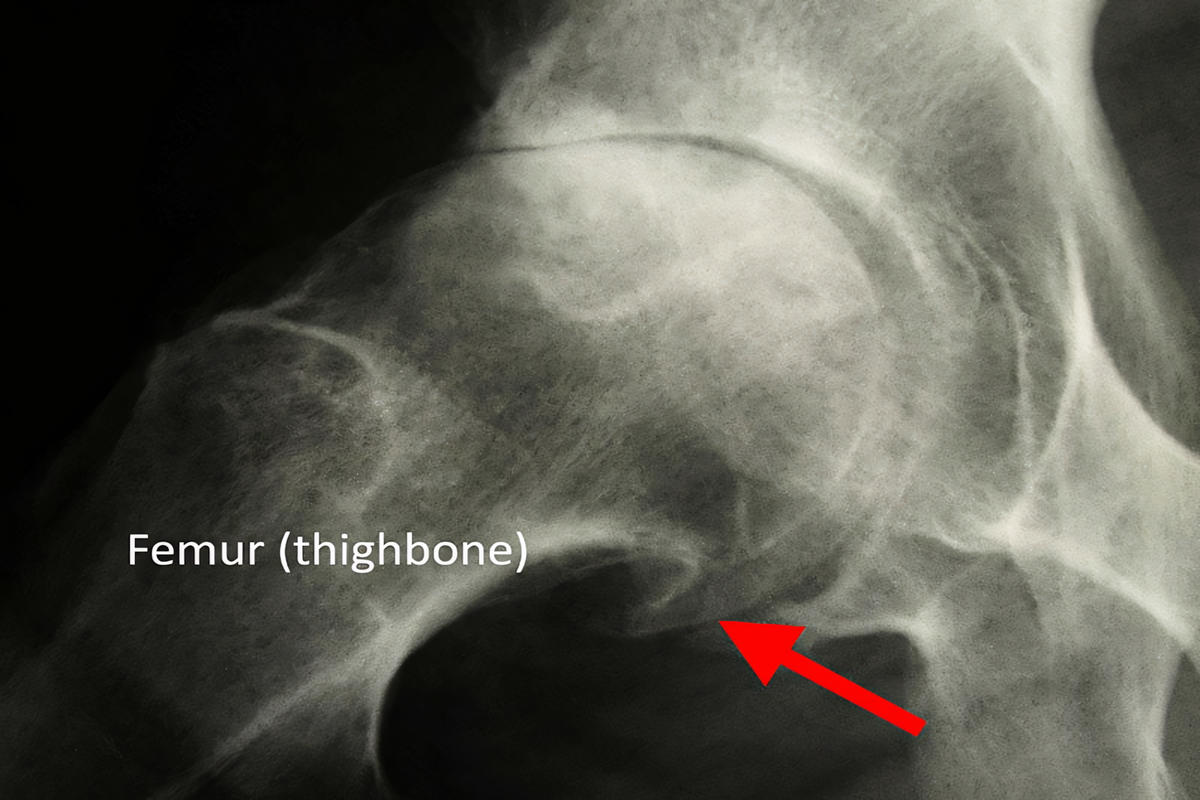

Ακτινογραφία ισχίου αποτελεί την εξέταση πρώτης γραμμής και αναδεικνύει:

Στένωση μεσάρθριου διαστήματος

Οστεόφυτα

Υποχόνδρια σκλήρυνση

Παραμόρφωση κεφαλής